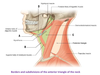

What is A?

Stylohyoid muscle

What is B?

Mandible